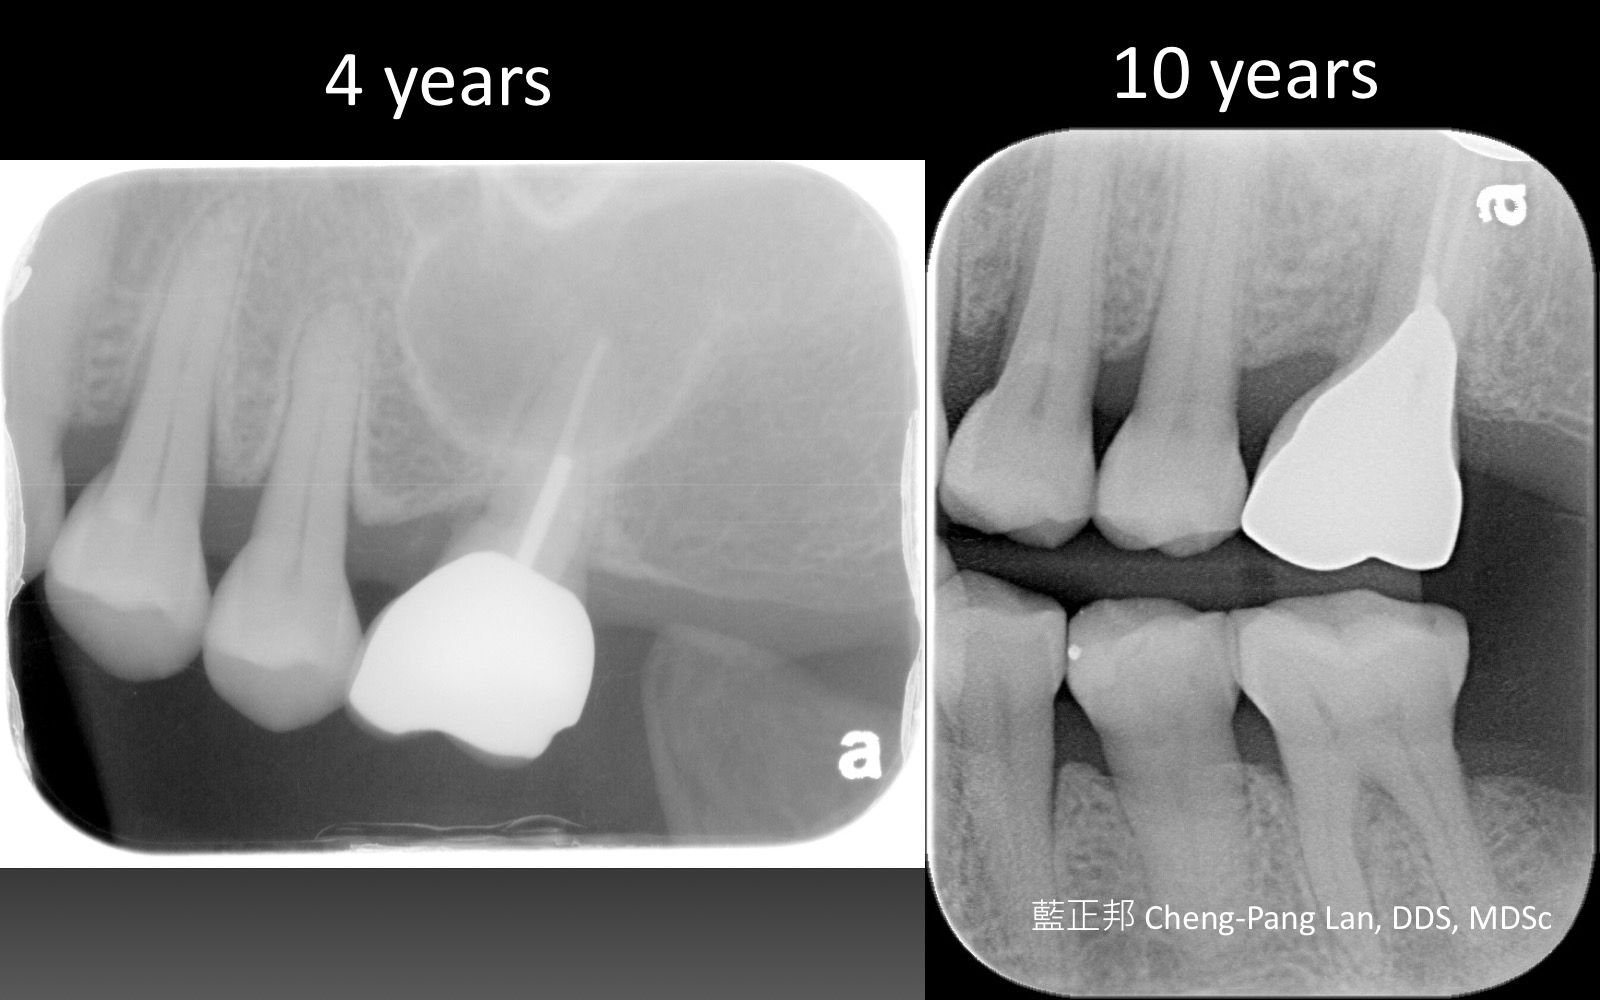

老師常常暗示著大家,implant與natural teeth之間,留下natural teeth比較好。這個我真的相信,在牙周病科的每一位學弟妹也都相信,甚至我相信週六在場的牙周病醫師都認同,但是大家有沒有想過,每隔週三一起開會的Prosthodontist、 Orthodontist都相信嗎?甚至,從實習醫師畢業就進入職場服務病人的學弟妹們,都相信嗎?